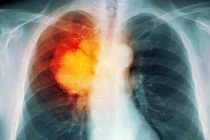

Một bác sĩ thuộc Bệnh viện Ung thư Giang Tô cho biết, bé gái này sống gần đường cao tốc ở tỉnh Giang Tô và đã hít phải khói bụi độc hại trong một thời gian dài.

Theo Tổ chức Ung thư Mỹ, bệnh ung thư phổi hầu như không bao giờ xảy ra ở trẻ em. Tuy nhiên các số liệu chính thức cho biết số người mắc bệnh ung thư phổi tại Trung Quốc đã tăng vọt trong thời gian qua do chất lượng không khí ngày càng suy giảm, đặc biệt ở các thành phố lớn.

Bộ Y tế Trung Quốc cho biết, số người chết vì ung thư phổi ở nước này đã tăng hơn 400% trong vòng 30 năm qua. Ung thư là nguyên nhân gây chết người nhiều nhất ở Thủ đô Bắc Kinh lúc nào cũng ngập tràn khói bụi.

Vụ cô bé 8 tuổi mắc bệnh ung thư phổi được công bố hai tuần sau vụ thành phố Cáp Nhĩ Tân ở tỉnh Hắc Long Giang phải đóng cửa do khói bụi ô nhiễm dày đặc. Khói bụi đã khiến cho tầm nhìn chỉ còn 50 m và buộc các trường học đóng cửa, hàng loạt chuyến bay phải hủy bỏ. Khi đó, tỷ lệ bụi độc hại trong không khí PM 2,5 ở Cáp Nhĩ Tân tăng vọt lên 1.000 mg/m3, cao gấp 40 lần mức an toàn do Tổ chức Y tế thế giới (WHO) ban hành. PM 2,5 được cho là nguyên nhân gây nên các vấn đề sức khỏe, gồm cả ung thư phổi và bệnh tim.